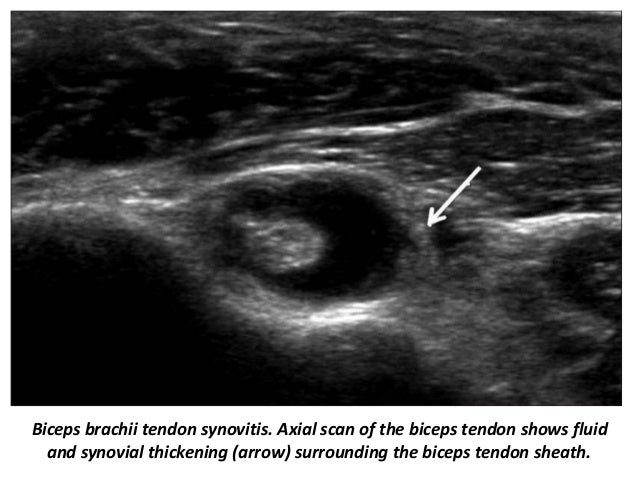

44. 44. Biceps brachii tendon synovitis. Axial scan of the biceps tendon shows fluid and synovial thickening (arrow) surrounding the biceps tendon sheath.